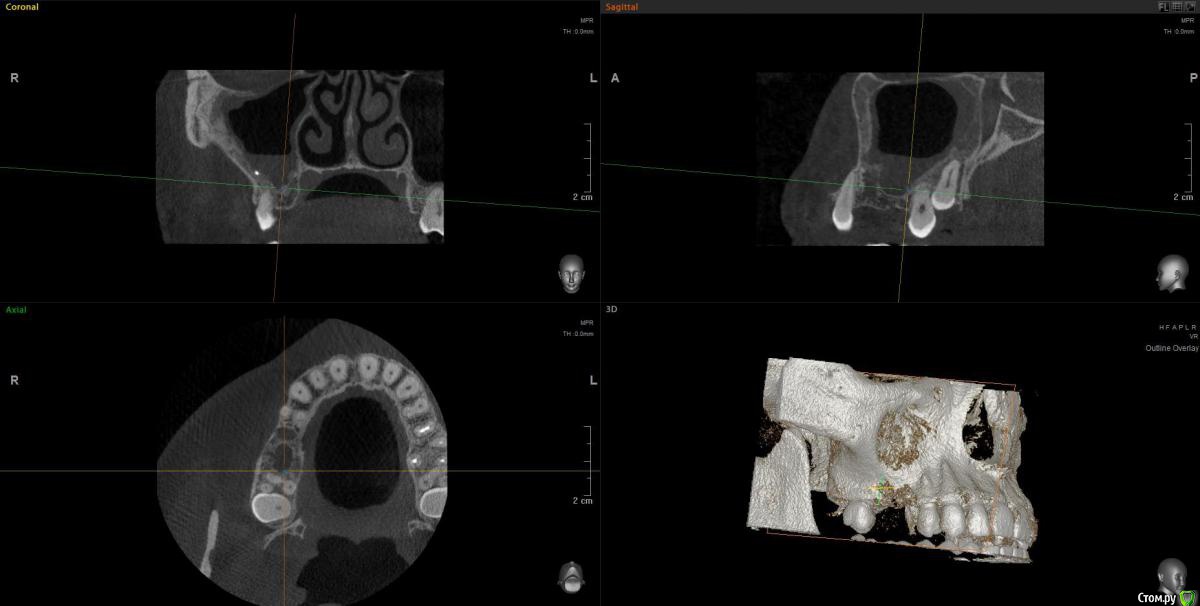

wladdX Опубликовано 30 июня, 2020 Поделиться Опубликовано 30 июня, 2020 Несколько скриншотов из КЛКТ 2 Ссылка на комментарий

колесников Опубликовано 30 июня, 2020 Поделиться Опубликовано 30 июня, 2020 Есть жидкость в пазухе на момент снимка. Можно только предполагать что является причиной воспаления,полной картины нет. Возможно это рельеф дна пазухи. В области 6ки углубление,где как в колодце застаивается слизь и прочее что попадает в полость и естественного дренажа не происходит. Я бы рекомендовал поставить 2 импланта 5,6. В области 6го провести закрытый синуслифтинг. Рельеф дна пазухи выровняется и вероятно обострений больше не будет. По крайней мере процессы происходящие в пазухе никак не повлияют на имплантацию,тогда как имплантация может купировать процессы в пазухе. Ссылка на комментарий

Оvzaika Опубликовано 1 июля, 2020 Автор Поделиться Опубликовано 1 июля, 2020 Несколько скриншотов из КЛКТ 25_1.jpg25_2.jpg26_1.jpg26_2.jpgH_M.jpgСпасибо! Ссылка на комментарий